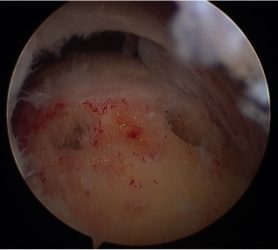

Arthroscopic image of rotator cuff tear.

The procedure is performed under a combination of general and regional anaesthesia. Most rotator cuff repairs are performed arthroscopically but repair of some large tears may be carried out through an “open” procedure. The inside of the joint and subacromial bursa are examined. A small amount of bone is removed from the undersurface of the acromion. The bone where the tendon normally attaches is freshened to promote bleeding and facilitate healing. The tendon is then fixed back to bone with suture anchors.